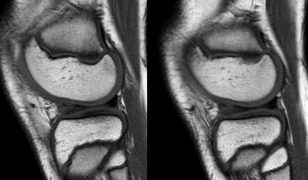

Le ménisque discoïde est une malformation congénitale rare du ménisque.Cette dysplasie méniscale touche presque exclusivement le ménisque latéral.Son diagnostic 'académique' en IRM repose sur la visualisation de la continuité des cornes antérieure et postérieure sur des clichés sagittaux en au moins 3 coupes consécutives de 5 mm d'épaisseur (Fig. 2).Ces résultats sont ajustés en fonction des paramètres partiels utilisés.

Figure 2 Ménisque latéral discoïde.Image sagittale pondérée en T1.Continuité des angles avant et arrière sur 3 profilés fixes consécutifs de 5 mm.Notez la dégénérescence myxoïde de la corne antérieure de ce ménisque discoïde.